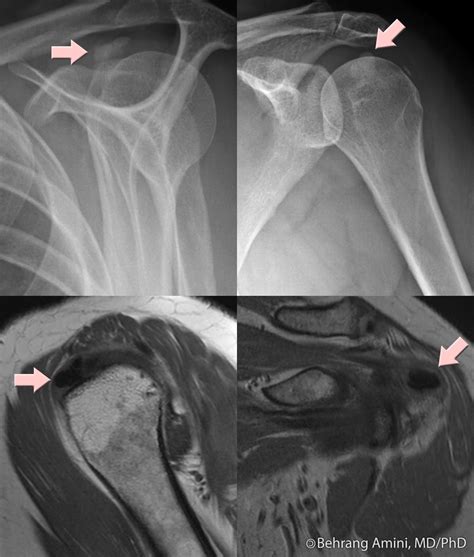

HADD can affect various joints, including the shoulder, elbow, wrist, hip, knee, and ankle. It can also occur in soft tissues such as tendons and ligaments. The most commonly affected areas are the shoulder and the wrist.

Diagnosing HADD involves a combination of clinical evaluation, imaging studies, and laboratory tests. The diagnostic process typically includes the following steps:

• Imaging Studies: X-rays, ultrasound, and magnetic resonance imaging (MRI) can help identify the presence of hydroxyapatite crystals and assess the extent of the deposits.

Imaging studies are particularly important in diagnosing HADD. X-rays can show calcifications in the affected areas, while ultrasound and MRI provide more detailed images of the soft tissues and joints. Laboratory tests can help rule out other conditions that may cause similar symptoms.